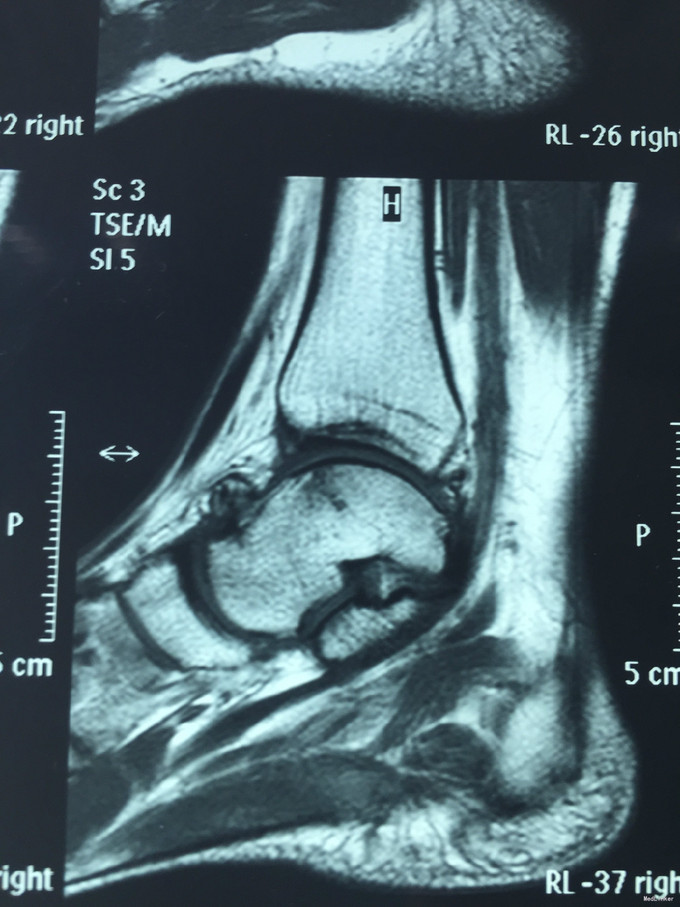

主诉:右踝扭伤后疼痛3年,伴活动受限2年。 现病史:患者男性,24岁。3年前,患者运动时扭伤右踝,无出血。患者当时至外院就诊,予消炎药物保守治疗,疼痛缓解。2年余前患者出现右踝活动受限,以背屈受限明显,伴右踝疼痛,无发热、盗汗,无其它关节痛,无晨僵等。2年来患者自觉右踝疼痛及活动受限症状逐渐加重。外院查MRI示:右胫骨远端前方骨质增生、右距骨前方骨性隆起、右踝关节内积液。我院查右踝X线示:右距骨前下方骨质密度增高、右胫骨前缘骨质增生。于我院就诊,门诊拟"右踝前方撞击综合征、右距骨骨软骨瘤、右踝滑膜炎"收入院。

查体:左下肢、双上肢肌力及活动度正常。右腓肠肌稍萎缩,右踝无明显肿胀。右踝关节跖屈、背屈受限,右踝内侧及前方关节间隙压痛(+)。ADT(-),下蹲提踵试验(+),内翻试验(-)。右腓肠肌肌力、肌张力、感觉正常。 辅查:见现病史。图片见下。

入院诊断:右踝前方撞击综合征、右距骨骨软骨瘤、右踝滑膜炎 治疗:入院完善术前检查后行右踝关节镜下滑膜清理+前方撞击成形+距骨骨软骨瘤切除。